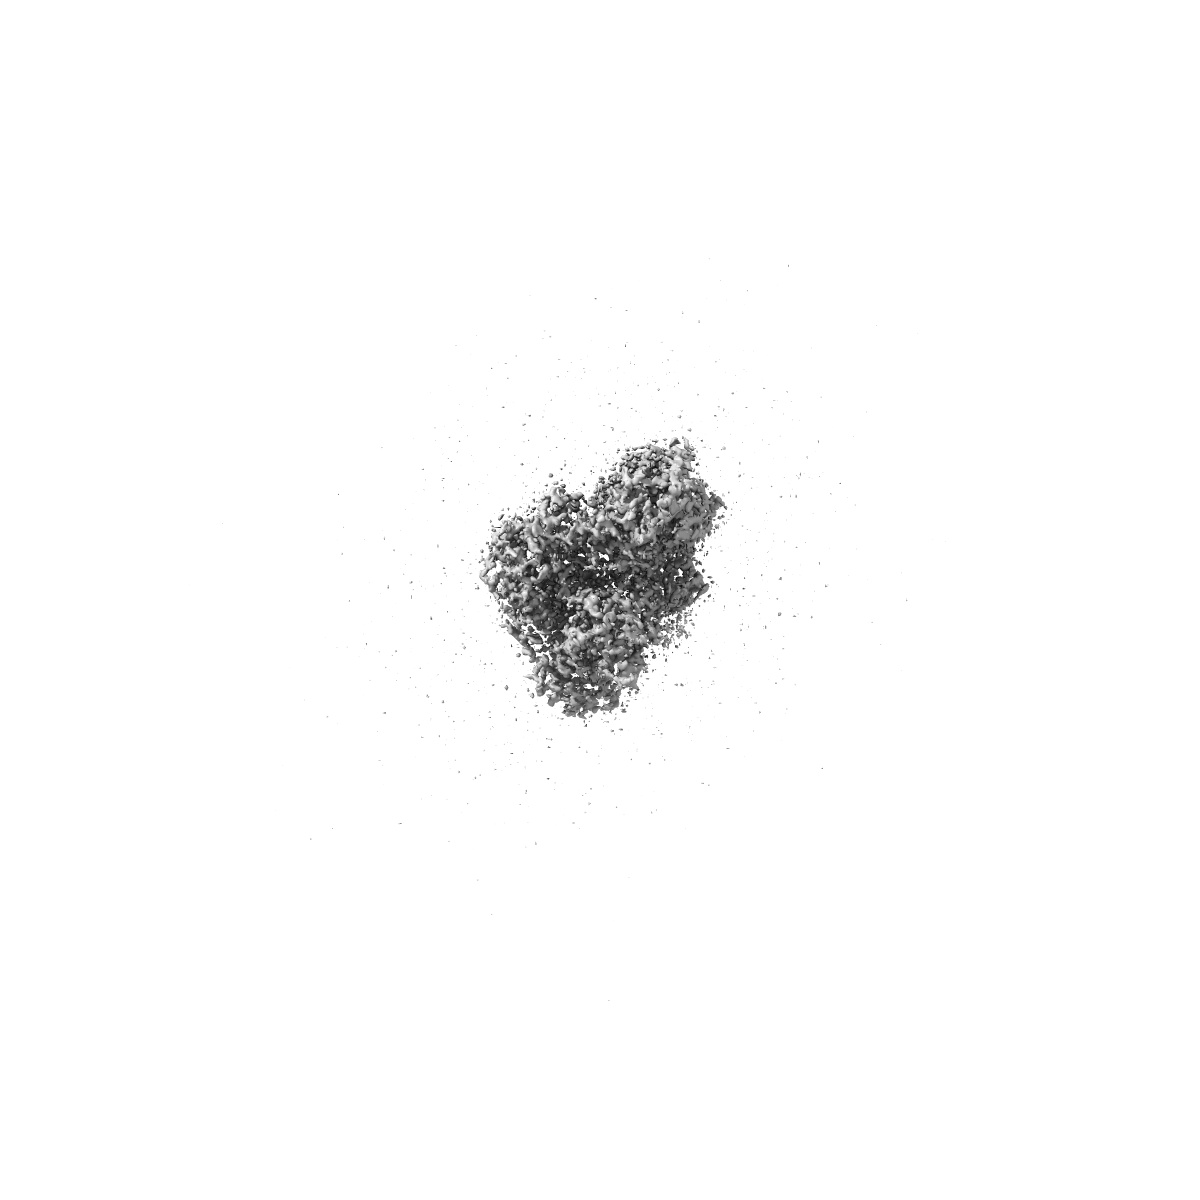

Cryo-EM structure of CAK in complex with inhibitor dinaciclib

Single-particle1.9 Å

Sample: CDK-activating kinase

High-resolution cryo-EM of the human CDK-activating kinase for structure-based drug design.